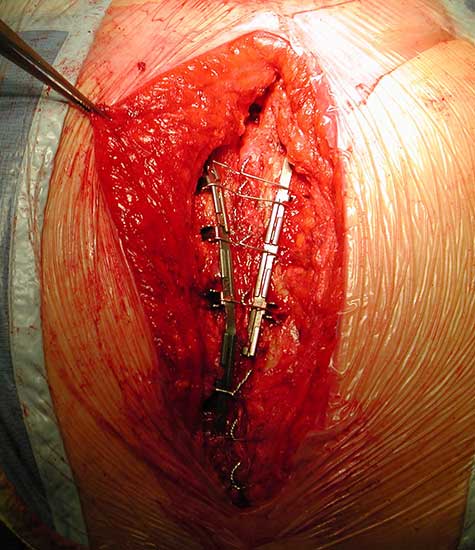

To facilitate insertion of the device, the fascia is dissected from the sternal border with electrocautery, and if necessary, perforating vessels are clipped (Figure 2). Once the fascia is mobilized, the hemisternum is elevated by two hand retractors to optimize exposure. The clips are assembled to form a device of a suitable length (up to 5 clips for each one) and the vertical segments of the clips are inserted into the intercostals spaces (Figures 3, 4). The two pliable vertical “fingers” of each unit are then bent outwards to wrap around the ribs, so that the clips are held firmly in place (Figure 5; Video 3). Re-approximation of the sternum is then achieved by means of single interrupted stainless steel wires. Two to 3 are placed through the manubrium, and the others are placed around the grooved arms of the clips at the level of the intercostal spaces (Figures 6, 7). The fascia, subcutaneous layers, and skin are closed in a routine manner. The extra time required for placement of the reinforcement device decreases with experience, and in our hands is approximately 4 to 6 minutes for each hemisternum.

Figure 9. The device (constructed out of four units) is implanted, where the third clip is positioned corresponding to the fractured bone.